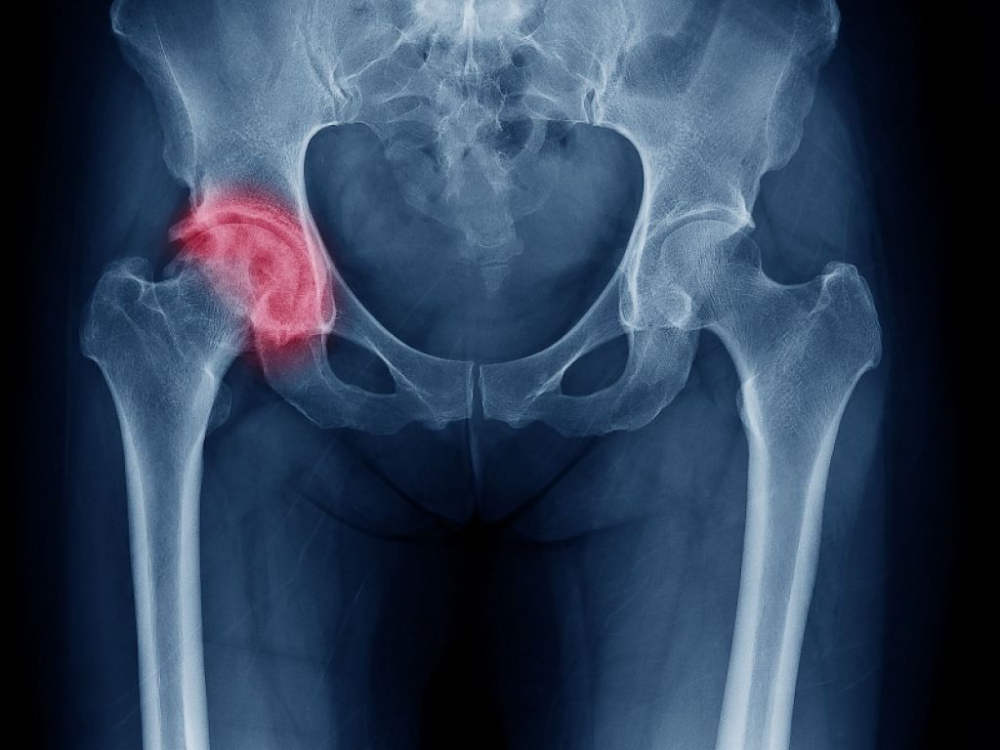

Inflamație a articulației șoldului, care cauzează durere și mers șchiopătat, sinovita de șold poate să apară la orice vârstă, dar este întâlnită în special la copiii cu vârste cuprinse între 2 și 8 ani, uneori chiar 10 ani.

Sinovita de șold este o inflamație a membranei care înconjoară articulația șoldului și apare după o infecție virală, cum ar fi nazofaringita, diareea sau o răceală obișnuită. De obicei, afectează doar un șold, dar e posibil ca inflamația să atingă ambele șolduri. Nu se cunoaște cauza exactă a apariției acestei afecțiuni.

Din cauza simptomelor similare, sinovita de șold poate fi confundată cu osteomielita acută, o inflamație a osului de cauză bacteriană sau cu osteocondrita, provocată de o necroză localizată. Pentru clarificare, copilului i se va face un examen clinic (medicul îi mișcă șoldurile, genunchii și alte articulații), după care poate fi indicată o radiografie, analize de sânge (pentru a se afla gradul de inflamare), o ecografie a șoldului sau un RMN.